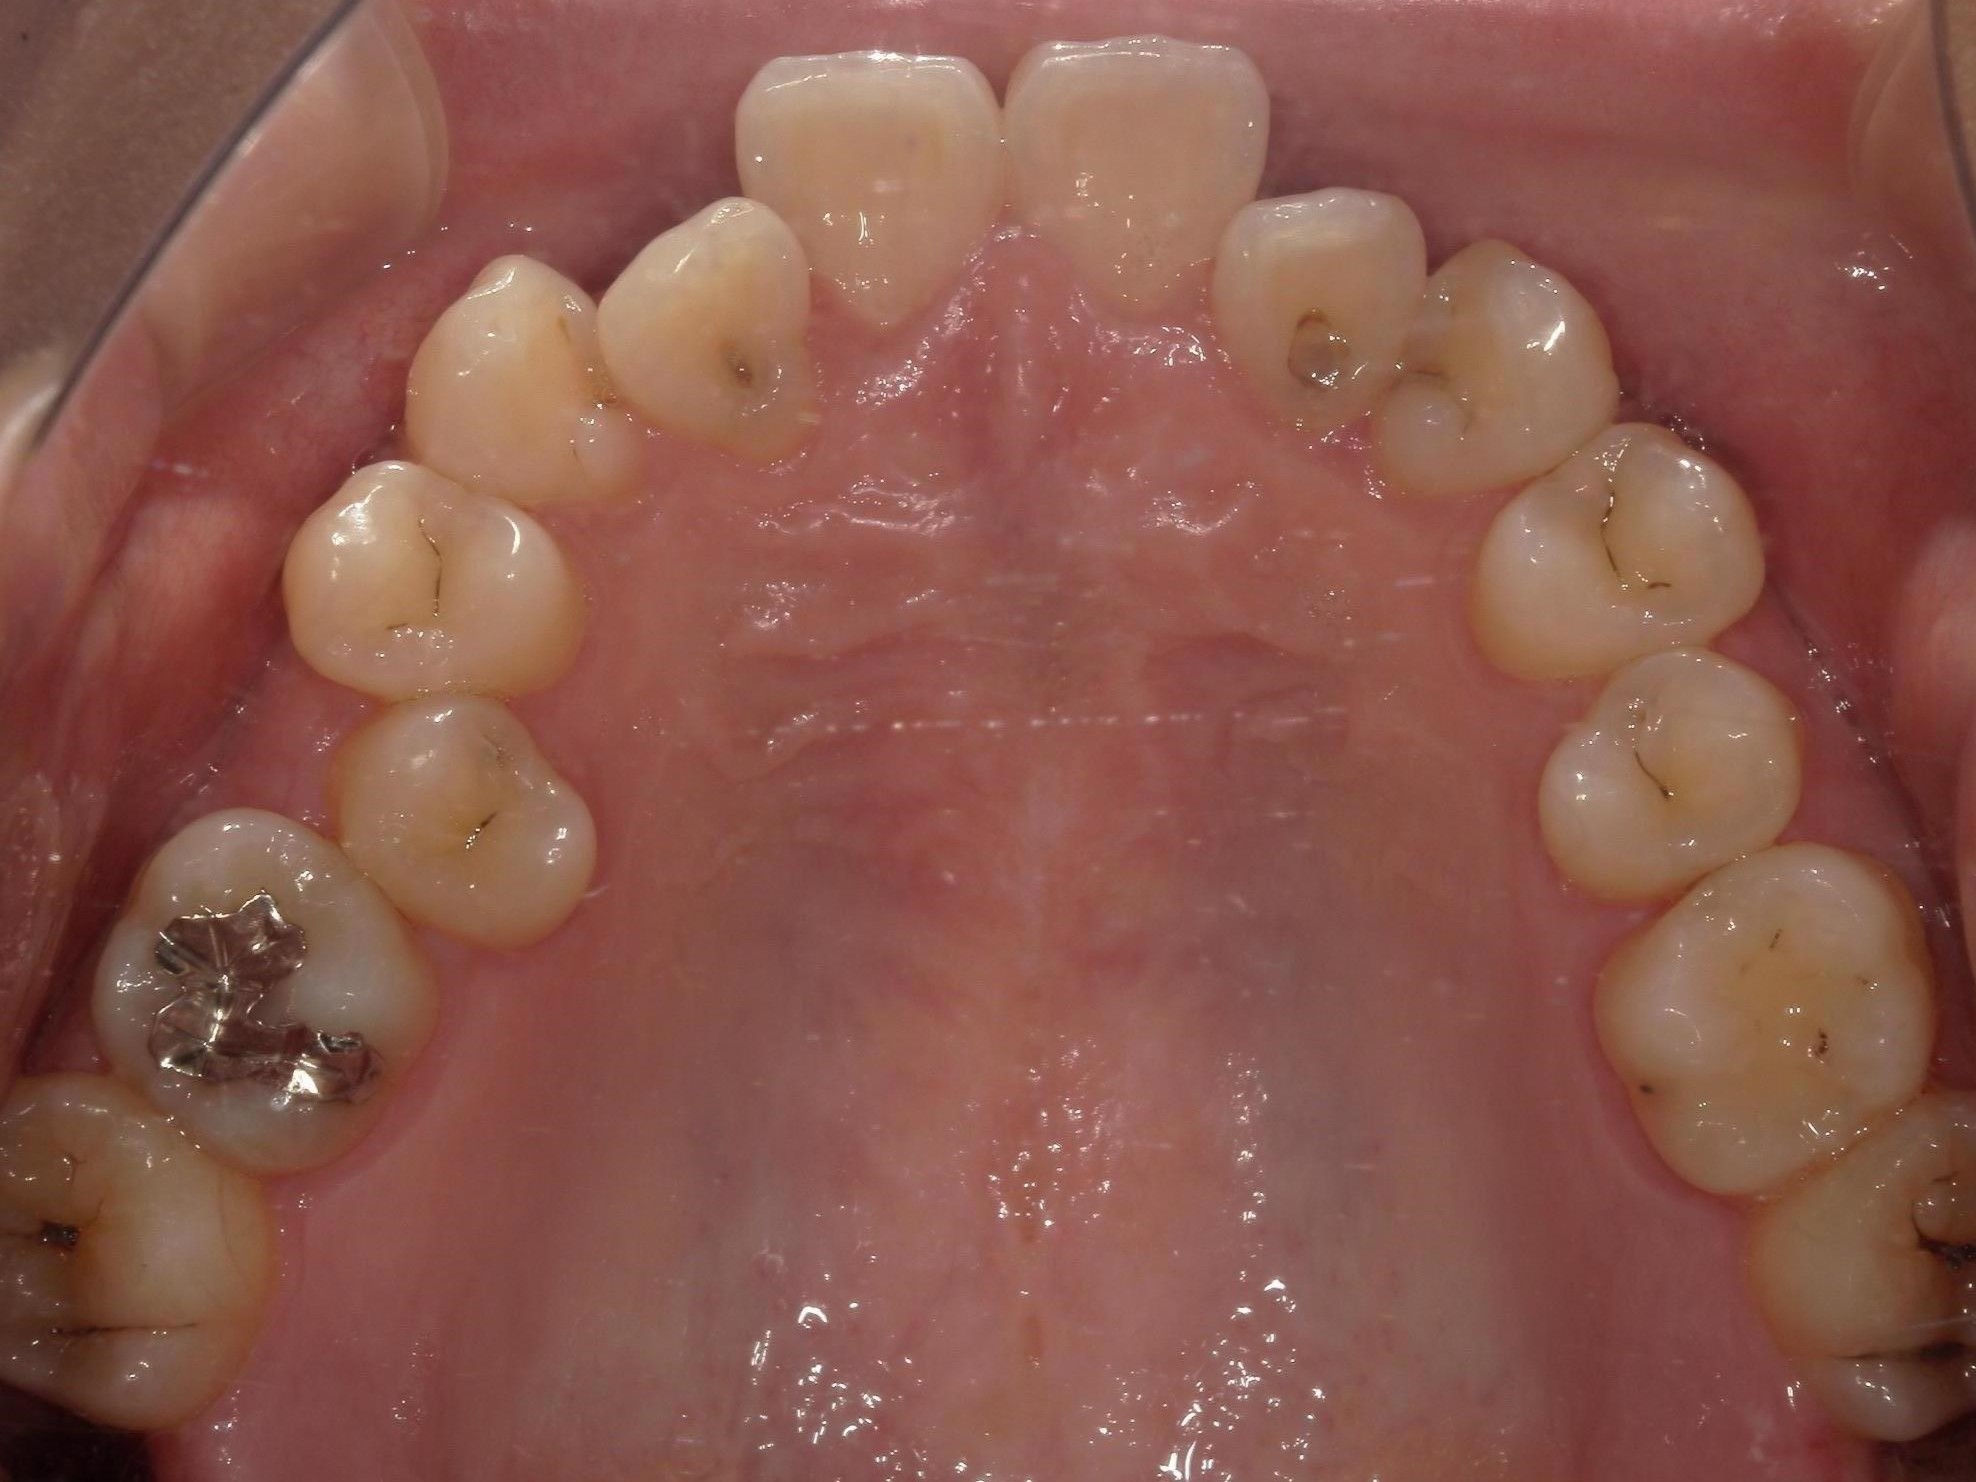

20代男性の方で、叢生・全体的な歯並び(不揃い・ガタガタ・不正咬合)が気になる患者様です。

歯が重なり合う状態は、見た目の問題だけではなく歯磨きが難しくなり虫歯や歯周病を引き起こすリスクにもなるため、インビザライン(重程度)矯正を行いました。

治療前